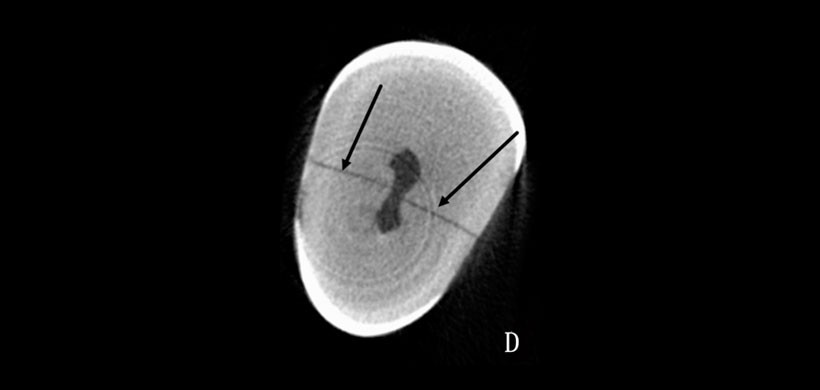

Para lo cual se utilizaron cuarenta y cuatro dientes con diferentes extensiones fisuras artificiales, creadas por exposición al nitrógeno líquido y después de agua caliente a 100 ° C. Posteriormente fueron sometidos a PR y CBCT. (Figura 1)

Para medir y registrar la profundidad de a grieta, se utilizó la microtomgrafia computarizada (miicro-CT), considerada como un examen relativamente más preciso que otros. La observaciones fueron realizadas por tres observadores, un estudiante graduado de endodoncia, un endodoncista y un radiólogo experimentado respectivamente, examinaron los resultados de PR y CBCT independientemente, y la presencia o ausencia de fisuras respectivamente. (Figura 2)